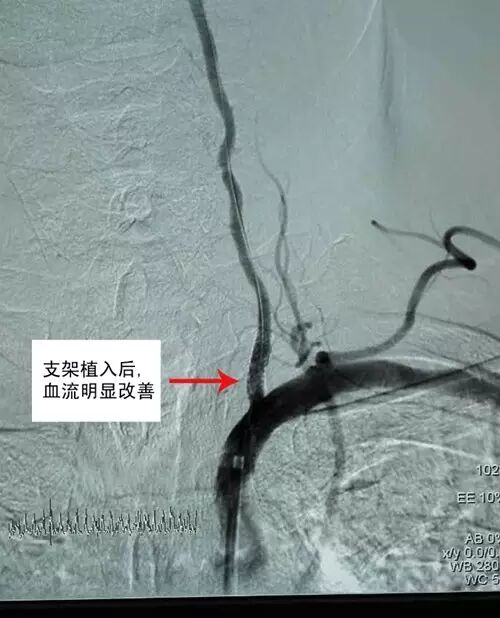

神经内科陶中海主任与家属反复沟通后,制定了详尽周密的治疗方案,为李大爷进行颈部动脉内支架植入术,术后患者恢复良好,头晕逐渐缓解,更重要的是,支架置入后通过物理压迫作用,稳定斑块,扩张狭窄的动脉,预防了严重中风的发生,患者很快好转出院。

血管支架植入术是一种微创治疗的新技术,该技术通过股动脉插管, 在DSA机器导引下将支架系统经过血管到达血管狭窄部位并释放,撑开血管,立竿见影的达到改善脏器供血,防治血管闭塞缺血的目的,该技术在心脑血管病治疗领域应用最为广泛。据美国统计,因颈部动脉斑块形成而发生脑中风者,大部分在中风前毫无症状。斑块脱落或者最终引起血管完全闭塞,可以导致中风残废甚至危及生命。这种疾病也可以通过手术进行血管内膜剥脱术治疗,但由于创伤以及风险较大,许多病人不愿意接受,而且对于狭窄位置较高或颅内病变者手术更无法到达。介入治疗创伤较小,颈部无手术疤痕,并发症风险相对低。